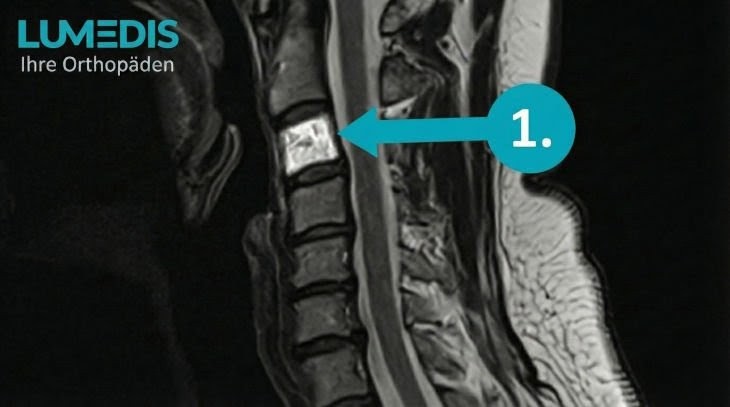

MRT der LWS T2 (linkes Bild)

Weiß kann man die Entzündung der Lendenwirbelsäule erkennen, da die Bandscheibe durch die Fehlstellung aufgebraucht wurde und nun Knochen auf Knochen reibt und eine Entzündung des Knochens entsteht.